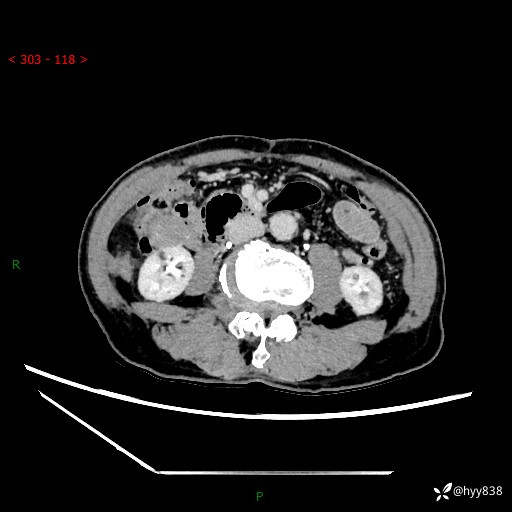

辅助检查:CT

临床诊断:肾肿物

肾脏CT平扫

增强(皮质期+髓质期+排泄期)

三期CT值:132hu 107hu 81hu